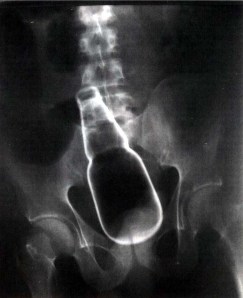

A 35-year-old man presented to the emergency department with profuse rectal bleeding, abdominal pain and an altered mental status. On physical examination, he was found to be intoxicated, with a blood pressure of 70/40 mm Hg, a pulse of 110 beats per minute, and an oxygen saturation of 90%. Abdominal examination revealed a mass and the presence of peritoneal signs. There was no evidence of trauma. A foreign body was found on rectal examination but was not visible. Once the patient was hemodynamically stable, plain-film radiography of the abdomen was performed, and an intact bottle was seen in the rectosigmold colon. Laparotomy revealed a glass bottle of beer lodged in the sigmoid colon, with multiple lacerations in the rectosigmold colon. The bottle was extracted, and Hartmann’s colostomy was performed. The patient was treated with broad-spectrum antibiotics and anagesics and underwent colorectal reanastomosis, after which the recovery was uneventful.